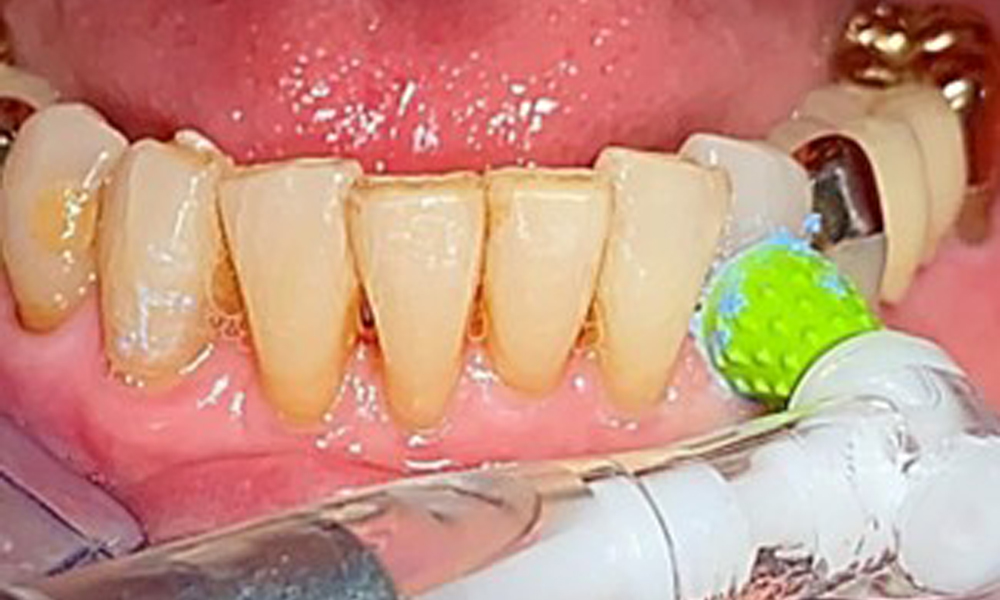

За отстраняване на зъбния камък и конкрементите по естествените зъби могат да се използват звукови/ултразвукови или конвенционални ръчни инструменти (8). За отстраняване на минерализираната плака от имплантите трябва да се използват титаниеви или пластмасови кюрети (фиг. 10), или пластмасова, или PEEK приставка (фиг. 11) по време на ултразвуковото лечение, за да се избегне увреждане на повърхностите на имплантите.

Трябва да се използва система за въздушно полиране с нискоабразивна пудра за отстраняване на биофилма от ръбовете на възстановяването, интерденталните зони и повърхностите на импланта (фиг. 12). Селективното полиране (фиг. 13) трябва да се използва за изглаждане на всички по-малко чувствителни зони, тъй като това намалява повторното прикрепване на бактерии (9).